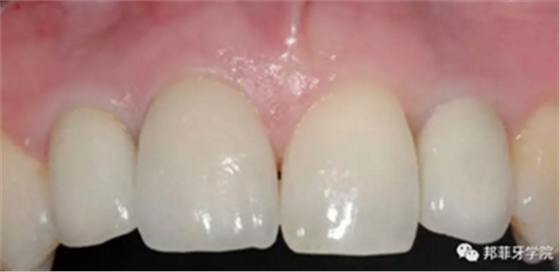

6年后效果穩(wěn)定,患者滿意(圖16)。

圖 16-1: 六年后復查

圖 16-2: 六年后復查